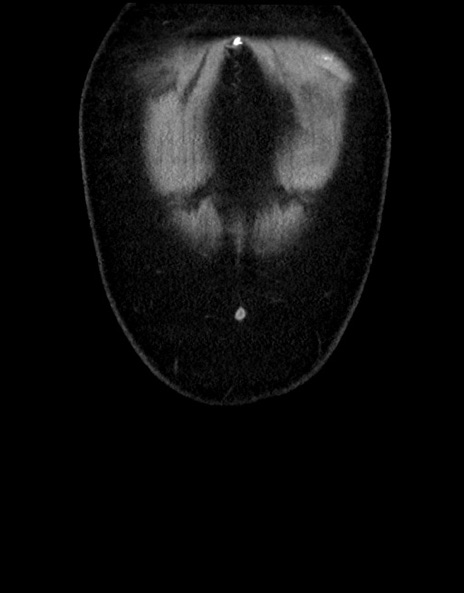

横断像

【症例】70歳代男性

【主訴】腹痛

【現病歴】今朝から腹痛あり。全体的に痛い。特に左上の方。排ガスが今日はない。冷や汗が出る。

【既往歴】直腸癌術後

【身体所見】左側腹部〜上腹部に圧痛あり。腹膜刺激症状明らかなではない。軽度反跳痛。左下腹部に術後瘢痕あり。

【データ】WBC 7700、CRP 0.02